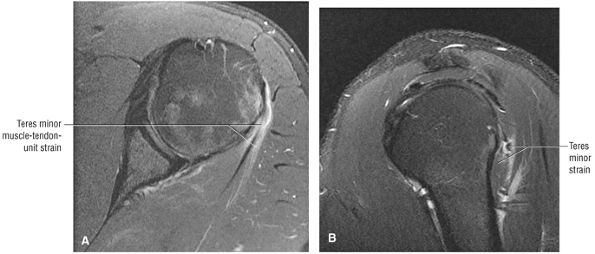

FIGURE 8.102 ● (A) The anterior undersurface of the acromion and the coracoacromial ligament form the coracoacromial arch. The subacromial subdeltoid bursa facilitates the passage of the rotator cuff and proximal humerus under the coracoacromial arch. (B) A superior axial image shows the anterior-to-posterior extent of the coracoacromial (CA) ligament perpendicular to the supraspinatus tendon. The fluid in the subacromial-subdeltoid bursa represents fluid between two serosal surfaces in contact with each other. One serosal surface is contributed by the undersurface of the coracoacromial arch and deltoid, and the other serosal surface is on the bursal side of the cuff.

|

![]() |

FIGURE 8.103 ● Pseudospur. The normal broad attachment of the coracoacromial ligament to the inferior surface of the acromion is shown on (A) T1-weighted coronal oblique and (B) sagittal oblique images. The low-signal-intensity acromial cortex (black arrows) and adjacent coracoacromial ligament and lateral slip of the deltoid attachment (white arrows) give the false impression of a small subacromial spur in the coronal plane. This pseudospur should not be misinterpreted as impingement; otherwise, unnecessary acromioplasties may be performed on patients with a normal coracoacromial ligament attachment and no associated acromial spurs.